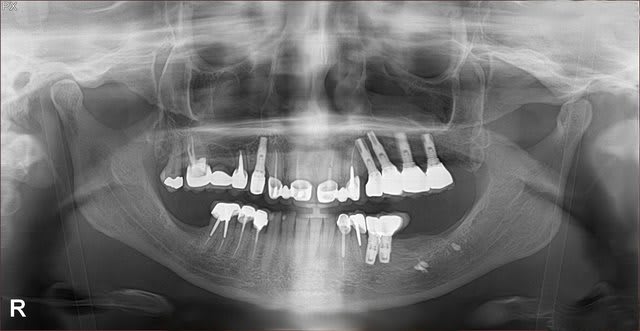

Je lui ai refait un bridge 15-17 en 2006 (un de mes premiers cas en cabinet privé) car la ceramique sur le precedent s'etait fracturee.

La racine de 15 était deja tres tres petite et trop mobile pour assurer une perennite correcte de la prothese lors du jour de la refection du bridge en 2006, mais j'etais jeune praticien et le dentiste titulaire m'avait dit avec sa grosse voix " MAIS NOoooooooonn aucun probleme!"

PS: 17 n'avait a l'origine qu'une endo nulle. Je l'ai reprise sous digue evidemment. Le canal MV est reste introuvable mais la dent n'ayant jamais eu de symptomatologie j'ai laissé comme ca a l'epoque.

Pour le bridge, elle continue sa collection d'implants...

Fait gaffe, la 13 et la 12 sont moches aussi.

PS: remarquez la petite taille de la racine de 15 et son apex erodé. Une chir apicale d'apres vous? ou une resorption radiculaire d'origine inflammatoire?

C'est ce que j'allais te demander, pourquoi cette racine est elle si courte, ni a t'il pas déjà eu une résection apicale?